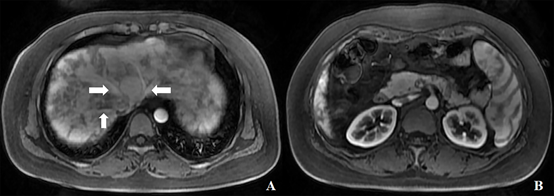

图2 钆塞酸二钠增强MRI动脉期图像。(A)三支肝静脉(箭头)早显;肝实质不均匀强化;(B)低于A图层面,双肾及脾脏强化特征提示该采集期相为动脉期。

图3 肝内多发结节。结节(长箭头)在T2WI呈稍低信号(A),增强后动脉期明显强化(C),肝胆期高摄取(F);结节中心瘢痕(短箭头)在T2WI呈稍高信号(A),肝胆期上低信号(F)。

A:T2WI压脂序列 B:T1WI增强前蒙片 C:动脉期 D:门脉期 E:过渡期 F:肝胆期。